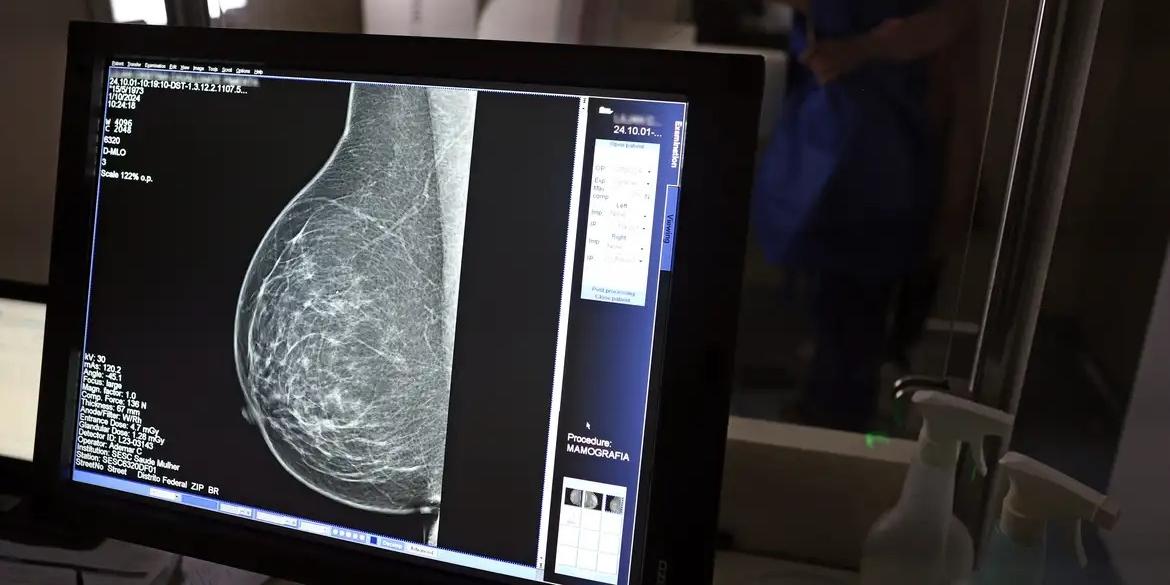

O Sistema Fecomércio Minas disponibiliza acesso gratuito a um dos exames fundamentais para detecção precoce do câncer de mama. Ação integra campanha Outubro Rosa e força importância do cuidado contínuo e preventivo com a saúde das mulheres. Atendimento é realizado na unidade Sesc Centro de Excelência em Saúde, na rua Viana do Castelo, 645, no bairro São Francisco.

O serviço é direcionado a mulheres de 50 e 69 anos e não é preciso apresentar pedido médico para conseguir realizar o exame. Pré-requisito vale somente para que está fora desse recorte etário.

Os agendamentos podem ser realizados até 22 de outubro pelo Portal de Serviços (portaldeservicos.sescmg.com.br) ou pelo App Sesc em Minas. Em caso de dúvidas, a pessoa pode entrar em contato pelo telefone: (31) 3270-8100.